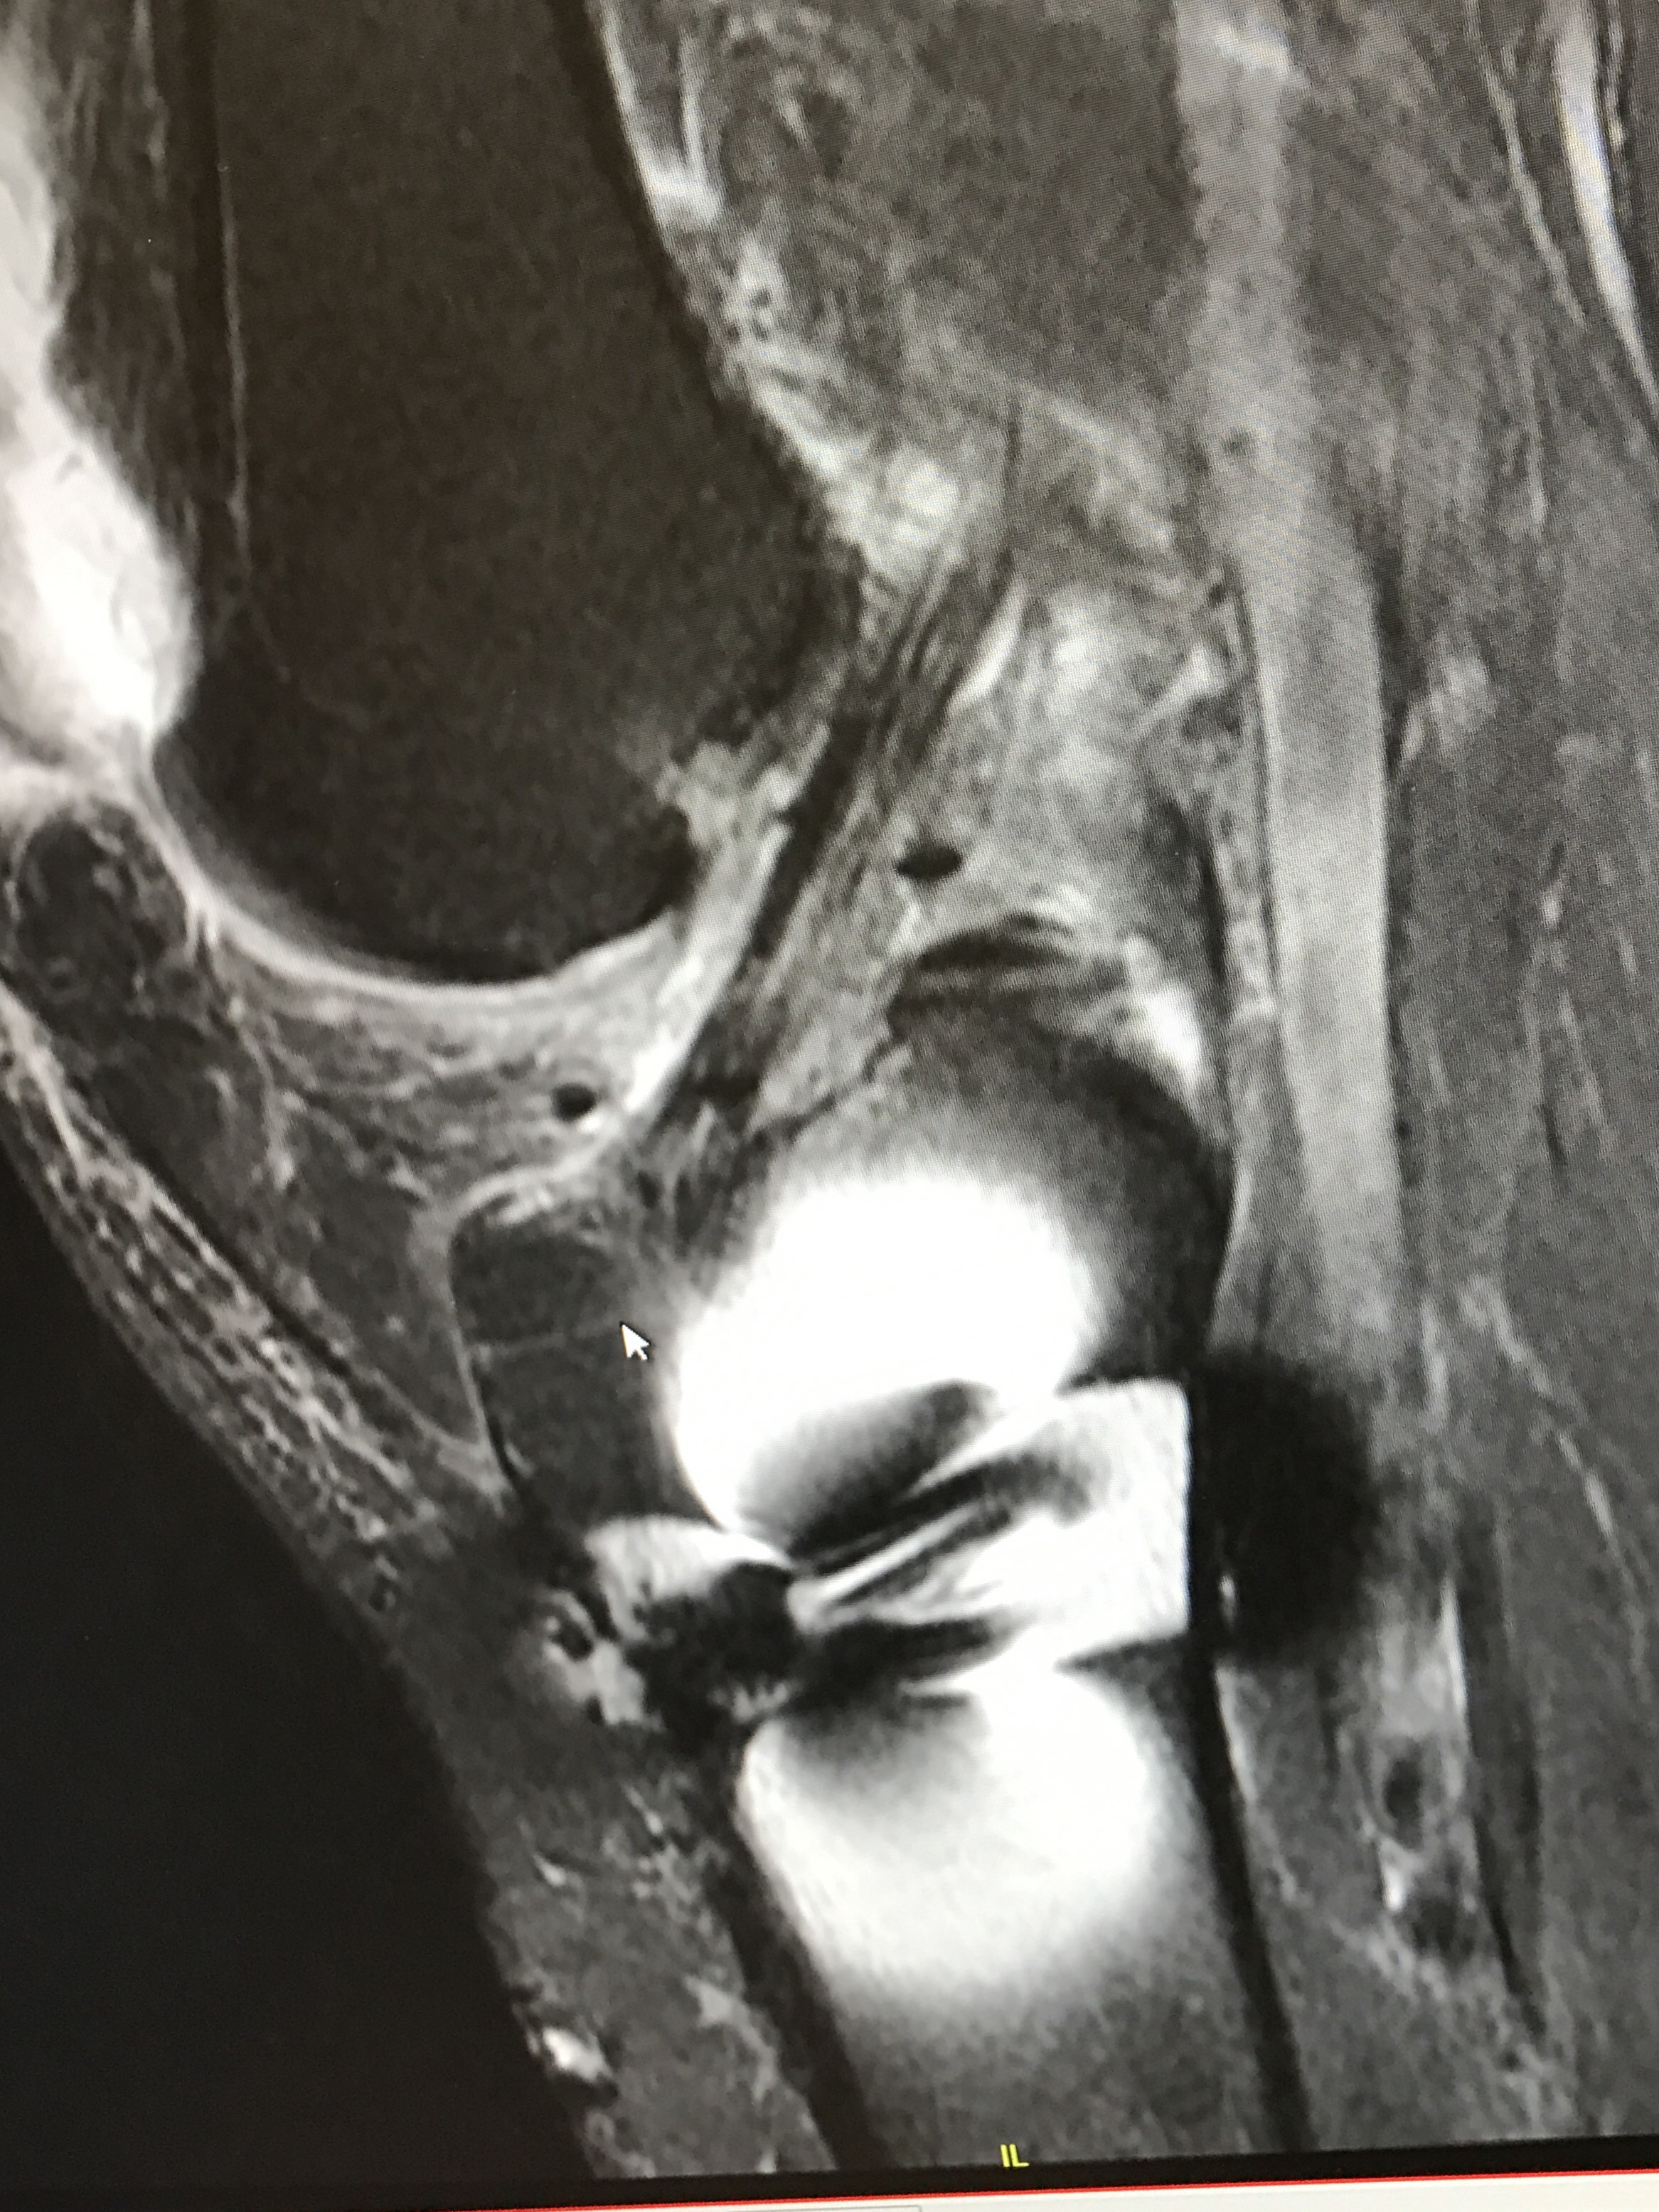

I feel like I took one for the team in D.C. (the team being humanity) when I climbed to the top of a cement pillar to get a bird’s eye photo of the march. Unfortunately, I misjudged the height and my jump to the ground resulted in almost a month of knee problems. The good news is that I now have some awesome photos of my knees, including the mysterious staple I received during an ACL repair. Enjoy!

MRI- the shiny area reflection from the staple!